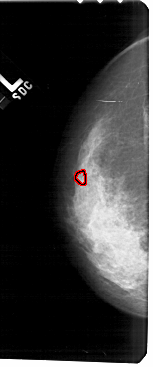

A_1238_1.LEFT_MLO

FILE: A_1238_1.LEFT_MLO.OVERLAY

TOTAL_ABNORMALITIES 1

ABNORMALITY 1

LESION_TYPE CALCIFICATION TYPE PLEOMORPHIC DISTRIBUTION CLUSTERED

ASSESSMENT 4

SUBTLETY 3

PATHOLOGY MALIGNANT

TOTAL_OUTLINES 1

BOUNDARY